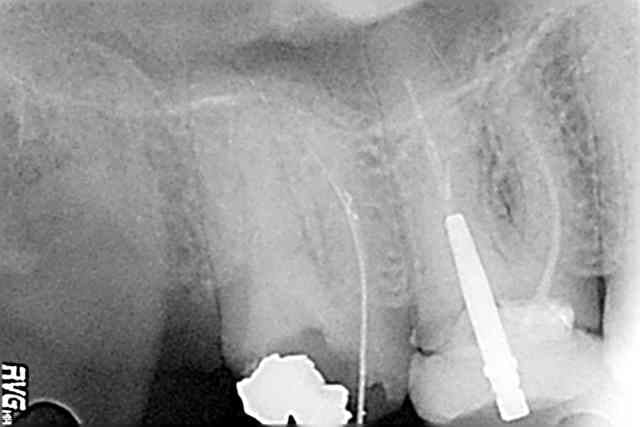

En fait il y avait 3 instruments un fragment long de M Two, et deux fragments de Limes H.

je pense que le praticien qui m'a adressé le patient a essaye de deposer le fragement log en essayant de le by passer avec des limes H et en a fracturé deux autres.

je l'ai dégage aux Ultra sons avec les Inserts Carr Killer, puis fait vibrer gentiment en devissant.

pas utilisé d'instruments de prehension.

Le seul conseil que je peux donner sur un cas comme celui-ci, c'est d'essayer de comprendre pourquoi l'instrument s'est fracturé. En fracture haute comme ici, la contrainte est coronaire, notamment pour des instruments utilises en crown down sur toute leur hauteur.

J'ai cherche a supprimer la contrainte coronaire palatine, ce qui a degage l'instrument.

Ce ne marche pas a tous les coups, mais parfois ca sort...

Il est beau le cas Steph.

En revanche je suis quasiment sur que l'instrument n'est pas un Mtwo. celui la présente 3 angles de coupe, avec une sorte de méplat radiant. Il me fait pense plus à un K3.

Ca ne change rien au résultat, c'est juste une réflexion que je me suis fait en regardant la photo.

Ca peut d'ailleurs aussi bien etre un F3 ProTaper avec la section triangulaire concave

qui donne l'impression d'avoir des meplat radiant. Bien plus probable que K3. Tu peux lui demander ?

Ca ne change rien au traitement, juste par curiosite.